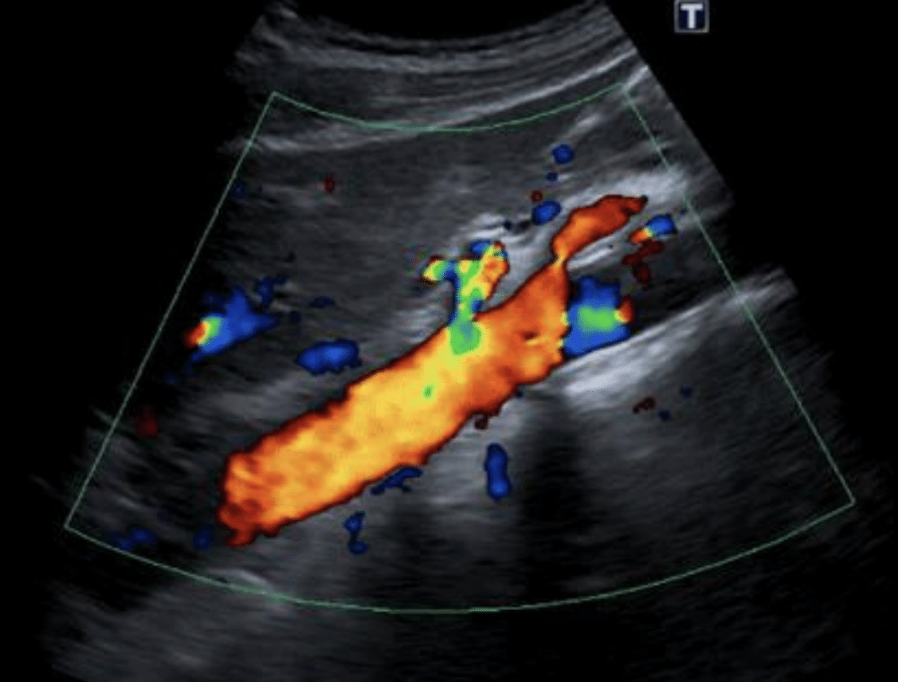

20

Q

Doppler en aorta abdominal y cava

A

Aneurismas

Trombosis